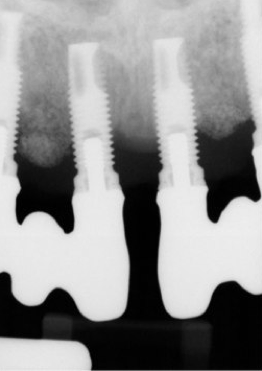

Given patient concerns about radiation exposure, it is important to know how, when, and why radiographs should be taken. Although there are concerns about radiation, radiographs make it possible to determine bone levels at baseline—ie, at implant and restoration insertion—and to monitor them over time. Vertical radiographs should be as parallel as possible to the implant body, so that the implant threads are clearly visible. Typically, periapicals should be taken once a year around dental implants. Figure 3 and Figure 4 shows bone loss up to the fifth and sixth thread.

Radiographs showing bone loss around an implant.

Figure 3

Figure 4